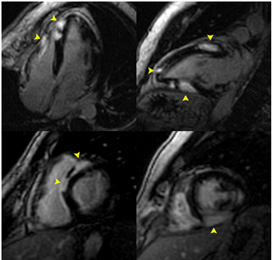

What is sarcoid in the heart?

Cardiac sarcoidosis is a rare inflammatory condition where groups of immune cells form granulomas in different areas of the heart which can cause issues from arrhythmia to heart failure.

How do you know if you have cardiac sarcoidosis?

Cardiac sarcoidosis: A heart under attack Fainting (syncope) Fatigue. Irregular heartbeats (arrhythmias) Rapid or fluttering heart beat (palpitations)

What can be done for cardiac sarcoidosis?

How is cardiac sarcoidosis treated?Implantable cardioverter defibrillator (ICD)Pacemaker.Catheter ablation.Heart transplant/left ventricular assist device.